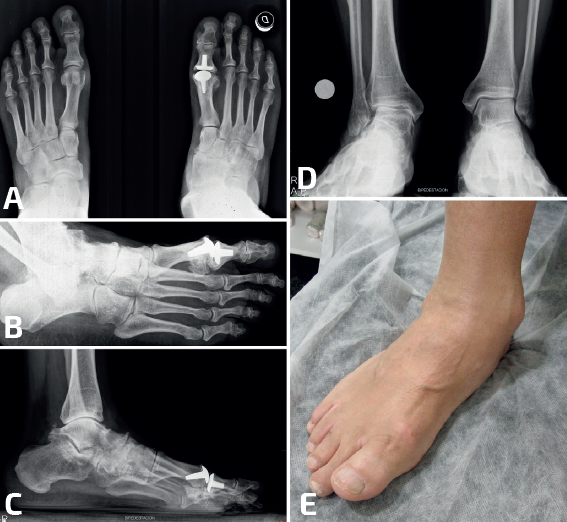

- Calcaneocuboidea: las coaliciones calcaneocuboideas suelen encontrarse en combinación con otras coaliciones (Frost y Pensieri) y también en el contexto de cuadros sindrómicos como el de Crouzon(26,27,28). Revisando nuestra casuística de coaliciones, los autores encontraron un caso de una paciente no sindrómica con una coalición aislada calcaneocuboidea bilateral que cursó con un pie plano valgo muy sintomático. La cirugía, consistente en una osteotomía varizante de calcáneo, mejoró la deformidad en valgo y la clínica hasta conseguir que la paciente estuviera asintomática (Figura 3).

- Corrección de la alineación, sin actuar sobre la coalición: en coaliciones óseas con deformidad (habitualmente en plano valgo). La osteotomía más habitual es la varizante de calcáneo, en coaliciones óseas talonaviculares, calcaneocuboideas y múltiples/masivas. Este tratamiento es el más frecuente en nuestra experiencia (Figura 6). Pero si existe un abducto del pie, una osteotomía de alargamiento de la columna lateral con una osteotomía de tipo Evans puede corregir la deformidad y mejorar el dolor. La supinación residual del antepié en coaliciones múltiples/masivas puede precisar de una plantarización del primer radio con una osteotomía de tipo Cotton. En pies con coaliciones tarsales masivas que originen tobillos cóncavo-convexo, las osteotomías supramealeolares permiten mejorar la valguización del retropié y la sintomatología dolorosa. El cambio de paradigma del tratamiento mediante cirugías de realineación sin actuar sobre la coalición ha derivado del tratamiento de las coaliciones talocalcáneas. De hecho, recientemente hemos formulado y publicado una nueva clasificación de coaliciones talocalcáneas con unas indicaciones de tratamiento que son extensibles a la mayoría de las coaliciones atípicas con una desaxación(64).